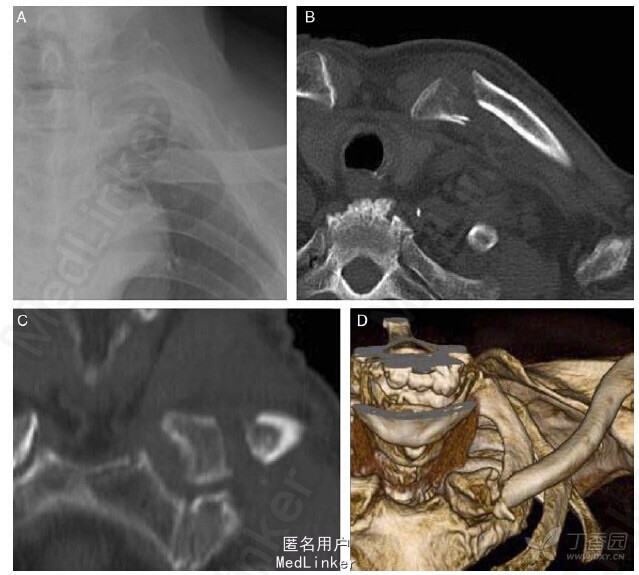

患者取仰卧位,沿着锁骨作一向锁骨内侧延伸的切口,暴露内侧锁骨。术中可见外侧骨折块向前移位,而内侧骨折块与胸锁关节相连。完成骨折块对位对线后,打入 3.0mm 空心皮质螺钉固定骨折部位,然后用 7 枚锁定螺钉把锁定钢板固定在锁骨内侧上方(图 2术中(A)和术后 X 线(B),左锁骨内侧骨折用皮质螺钉和锁定钢板固定。

骨折部位获得坚固的内固定后,无需限制患者上肢活动。术后随访 3 个月骨折部位愈合良好,未发现并发症。 因此,作者认为锁定钢板可有效治疗锁骨内侧骨折。